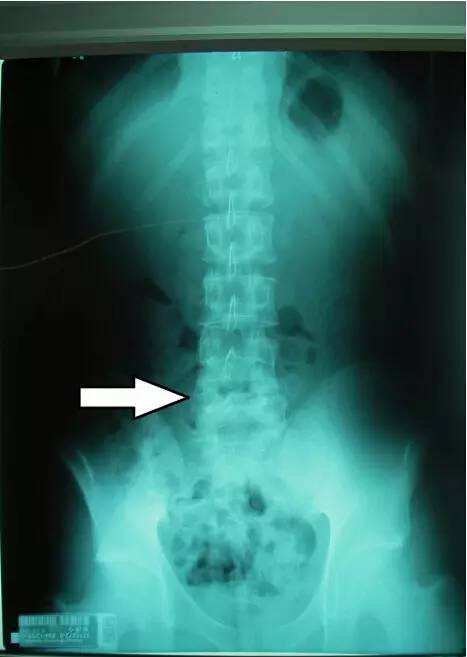

强直性脊柱炎在临床当中也有很高的发病率,这是一种主要累及脊柱 ...

强直性脊柱炎主要是身体里面的关节和脊柱附着点出现炎症导致的一 ...